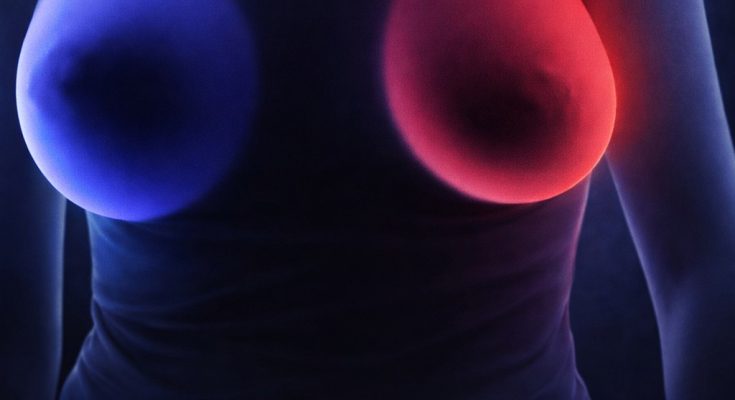

Within the breast, a variety of subtle transformations deserve close attention. Beyond the well-known presence of a lump, persistent localized pain, skin thickening, or sudden changes in the breast’s overall size or shape can be significant indicators. Other visual cues include redness, nipple discharge, or a distinct change in skin texture, such as dimpling that resembles the surface of an orange peel. While many of these symptoms are eventually linked to benign conditions like cysts or hormonal fluctuations, they should never be dismissed without a medical consultation.

The journey toward clarity begins with proper diagnostic testing. Physical examinations, ultrasounds, and mammograms allow healthcare providers to look beneath the surface, while biopsies offer the definitive answers needed to rule out or confirm a diagnosis. This transition from “observing” to “testing” is the most effective way to reduce health-related anxiety and ensure that if treatment is necessary, it begins without delay.